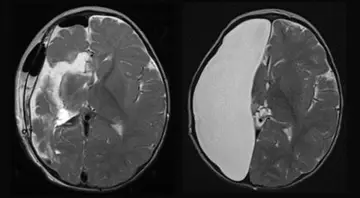

عملکرد افرادی که فقط یک نیمکره مغز دارند بی‌نقص است

پژوهشگران آمریکایی در بررسی جدید دریافتند عملکرد افرادی که فقط یک نیمکره مغز دارند،کامل است و نقصی ندارد.